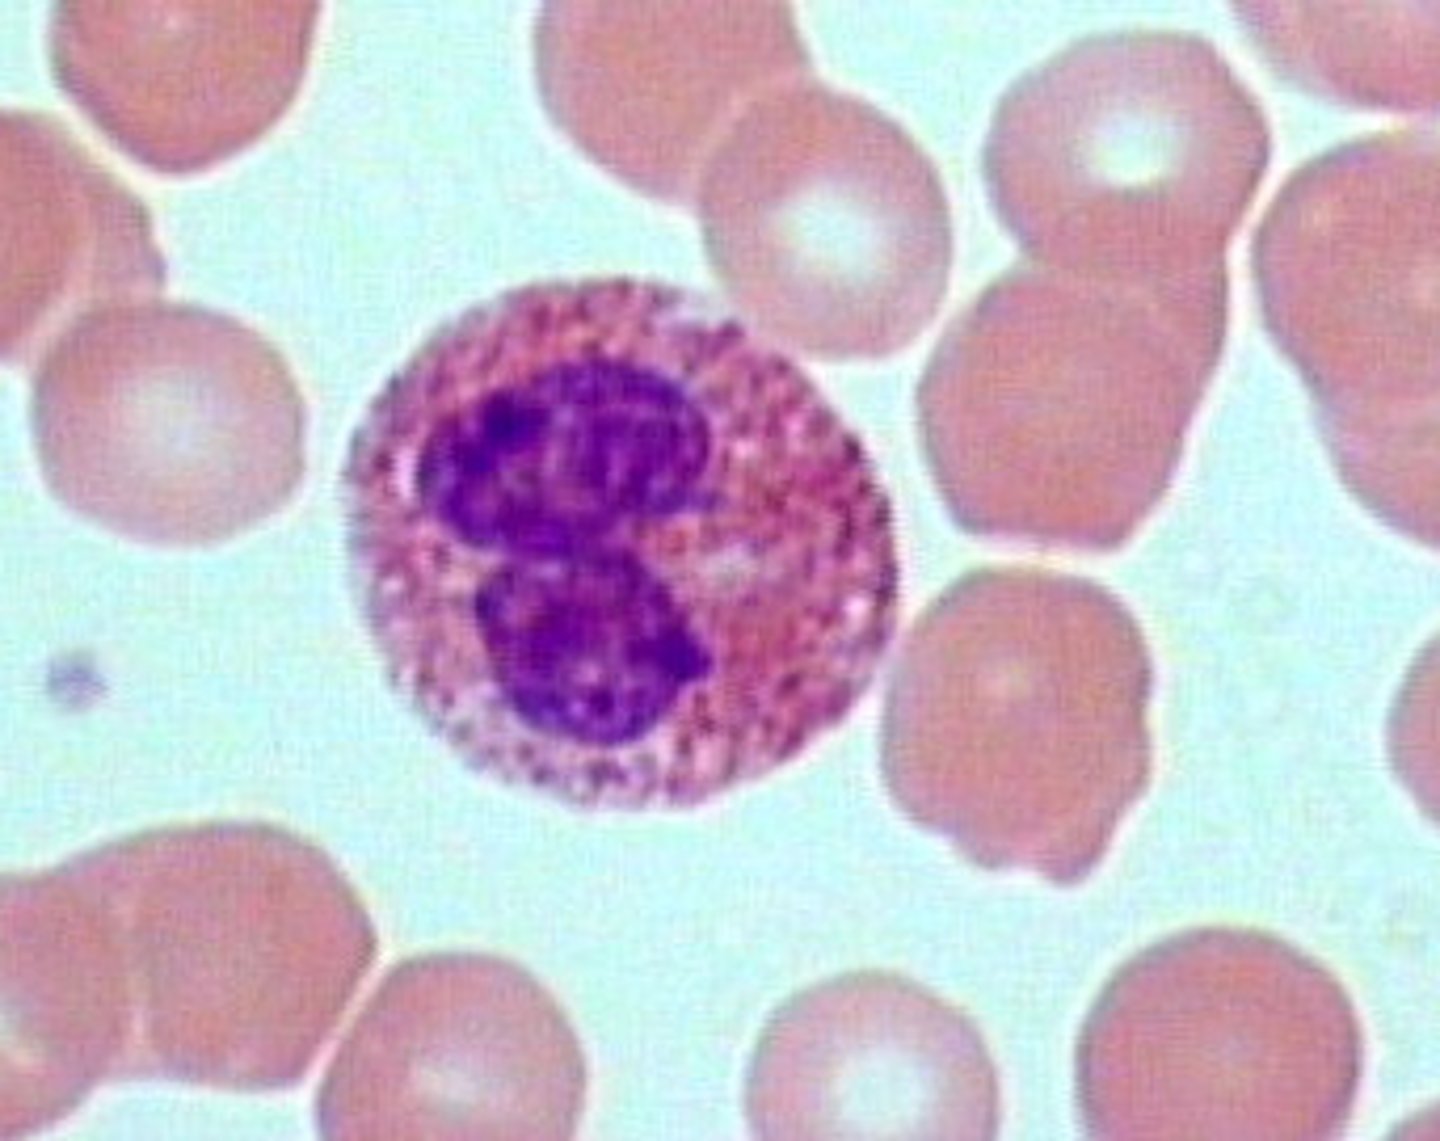

Neutrophils

Structure: Nuclei has three or more lobes, granules stain light pink

Function: The most common WBC; fights bacterial infections by engulfing bacteria by phagocytosis

Where does the name neutrophils come from?

Their granules do not stain with acid OR basic dye -- they are neutral

Other name for neutrophils

Polymorphonuclear leukocytes (bc they have many lobes)